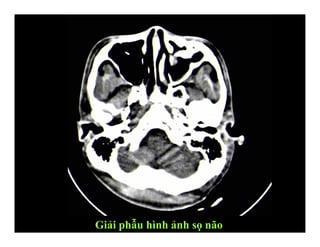

GIẢI PHẪU HÌNH ẢNH

SỌ NÃO

Giải phẫu hình ảnh sọ não

(1): Bao trong

(2): Đầu nhân đuôi

(3): Nhân bèo

(4): Đồi thị

(5): Não thất III

(6): Sừng trán não